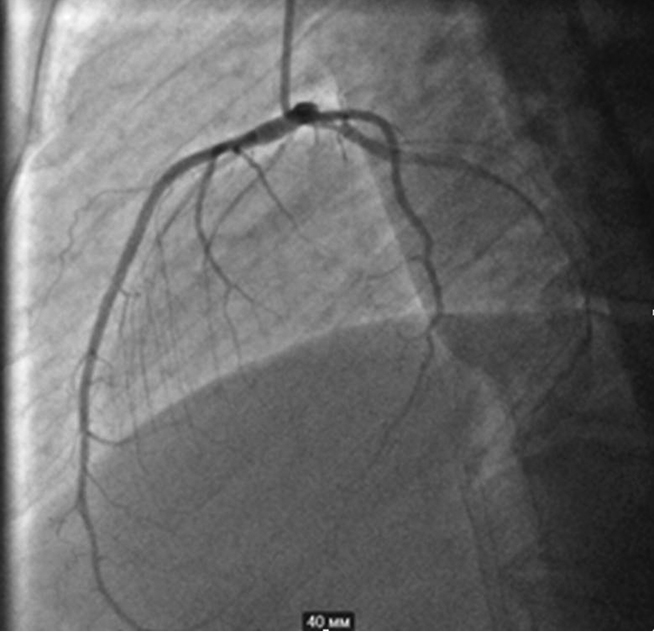

Taking into account his dyspnea on exertion and reduced exercise tolerance, the patient underwent coronary angiography, which revealed 75% proximal stenosis of the diagonal branch (D1) of his left anterior descending artery (LAD). His left circumflex coronary artery and right coronary artery didn’t have any significant stenosis (see Fig. 3 and 4). Conservative treatment was recommended in absence of indications for percutaneous coronary intervention (SYNTAX Score — 2 points).

Fig. 5. Right coronary artery without significant stenosis